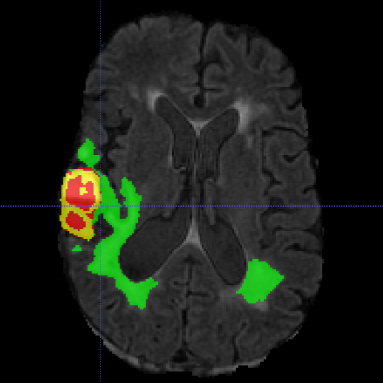

Multimodal Brain Tumor Segmentation Challenge (BraTS) aims to evaluate state-of-the-art methods for the segmentation of brain tumors by providing a 3D MRI dataset with ground truth tumor segmentation labels annotated by physicians [6, 11, 5, 3, 4]. This year, BraTS 2021 training dataset included 1251 cases, each with four 3D MRI modalities (T1, T1c, T2 and FLAIR) rigidly aligned, resampled to 1x1x1 mm isotropic resolution and skull-stripped. The input image size is 240x240x155. The data were collected from multiple institutions, using various MRI scanners. Annotations include 3 tumor subregions: the enhancing tumor, the peritumoral edema, and the necrotic and non-enhancing tumor core. The annotations were combined into 3 nested subregions: whole tumor (WT), tumor core (TC) and enhancing tumor (ET), as shown in Figure 1. Two additional datasets without the ground truth labels were provided for validation and testing. The validation dataset (219 cases) allowed multiple submissions and was designed for intermediate evaluations. The testing dataset (530 cases) will be analysed blindly using the docker submission, and is used to calculate the final challenge ranking.

Typically, the output result, even of a single model, is accurate as shown in Figure 1, however several cases still remain segmented imprecisely. Figure 2 shows an example of an incorrectly over-segmented whole tumor (WT) region, which is spilled over on the right side of the brain, most likely because the underlying MRI (Flair) has substantially higher intensity values in that region. More variability in training examples might have helped to solve the issue, or integration of anatomical knowledge of e.g. ”symmetrical highlights around ventricles are unlikely to be a tumor” , but such information is rather complicated to put inside of the network.